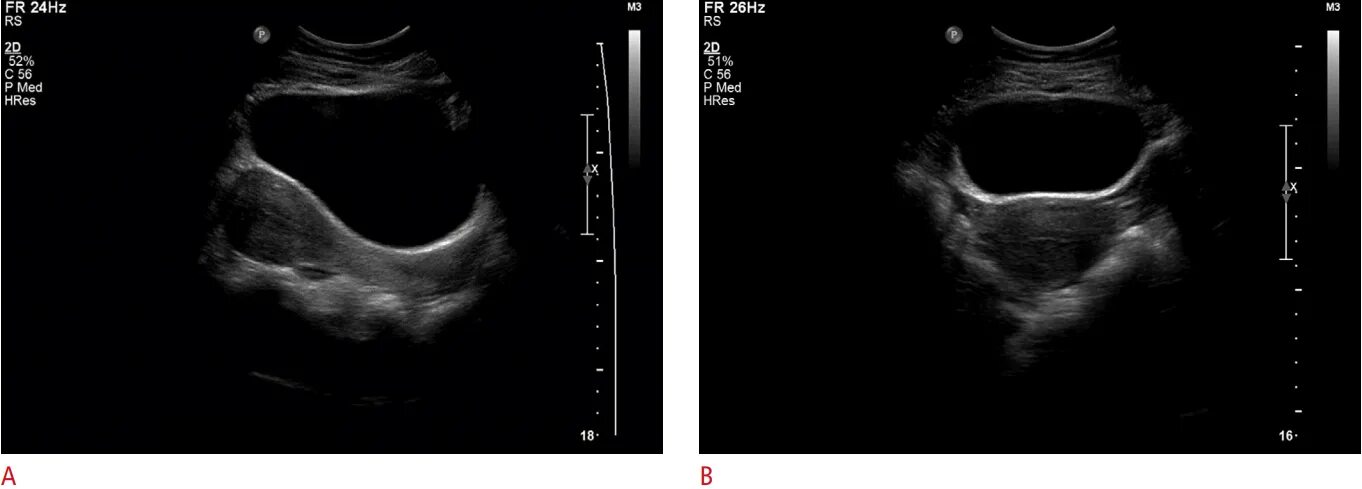

Трансабдоминальное узи